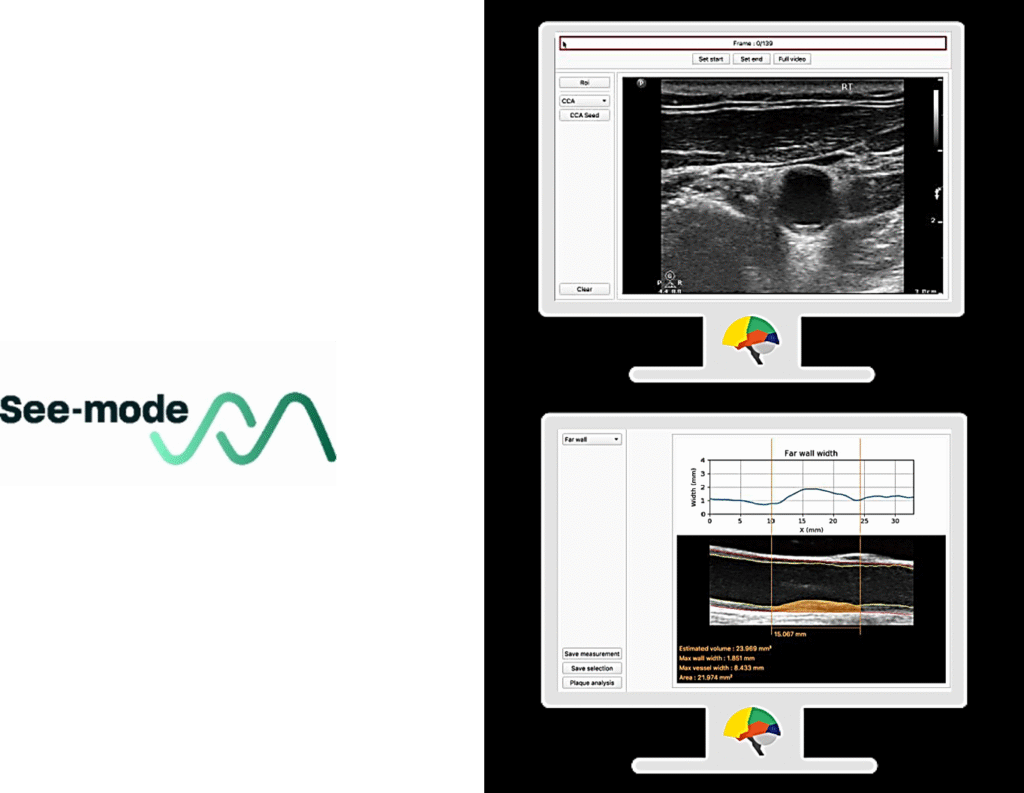

Other companies, such as See-Mode, apply machine learning to improve the interpretation of ultrasound images and predict stroke risk, while BrainQ is developing portable neurotherapy devices that deliver personalized electromagnetic stimulation based on individual brain data

Figure 6 See-Mode software.